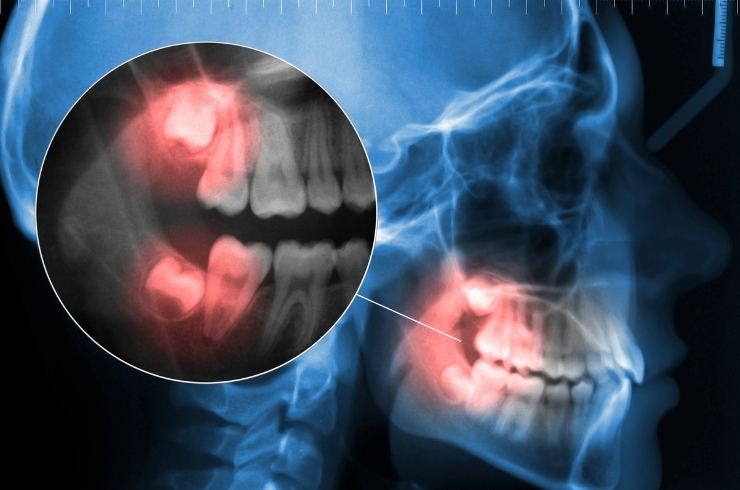

Impacted & Surgical Tooth Extraction

Safe removal of problematic teeth using precise techniques to relieve pain, prevent complications, and maintain oral health.

Wisdom Tooth Extraction

Safe removal of problematic wisdom teeth to prevent pain, infection, misalignment, and other complications while ensuring smooth healing and comfort.